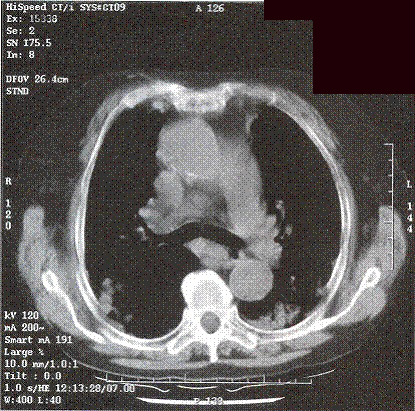

Complete blood picture showed mild neutrophilia. ESR was raised to 123mm/hr. She had mild renal impairment. Arterial blood gas on room air was nonnal on admission. Albumin/globulin ratio was reversed. Liver profile was normal. Sputum for culture grew oral flora and all smears for acid-fast bacilli were negative. CXR (Fig I) showed bilateral patchy opacity with nonnallung volume. No abnonnal mediastinal shadow was found. Old CXR of this patient was nonnal (Fig 2).

Figure 1